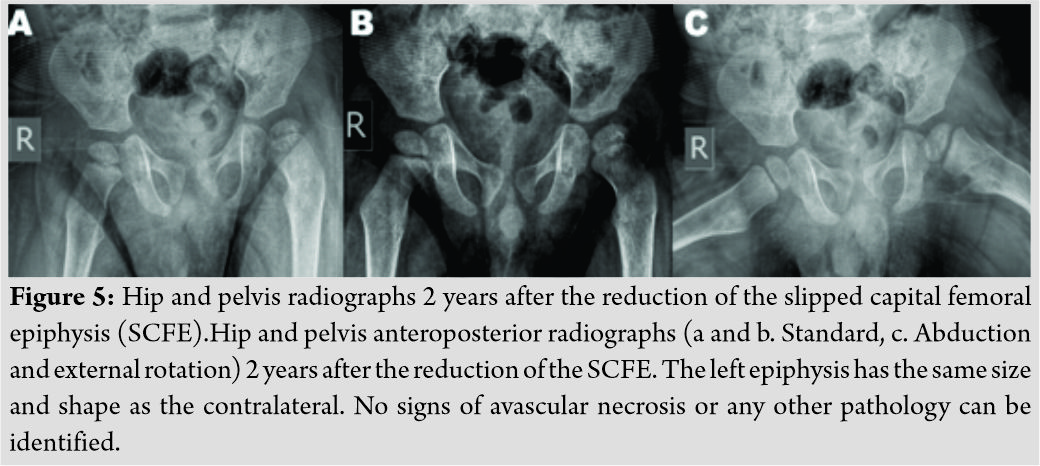

Approximately 6 h following his admittance to the hospital, the patient was transferred to the operating theater. Under general anesthesia, a gentle closed reduction was attempted, applying traction along the longitudinal axis of the limb and then internal rotation [8]. Successful reduction was confirmed with the use of a c-arm image intensifier and a hip spicacast with an anti-rotation bar was applied next (Fig. 3). On the next day, and because the patient continued to manifest epileptic seizures, despite the fact that he was receiving his usual treatment, he was transferred to the pediatric department, from where he was uneventfully discharged 4 days later.

The patient was followed up at our outpatients’ clinic every week for the 1stmonth and then every 15 days for another month. The spicacast was removed at 8 weeks (Fig. 4). Physical examination at this stage revealed a painless hip with a full range of motion. The patient’s physiotherapy and passive kinesiotherapy routine resumed at 6-month post-reduction. Despite the fact that he was not able to walk (and remained non-ambulatory on his latest follow-up visit) suffering from severe psychomotor dysfunction in the context of epileptic encephalopathy, painless hip range of motion was retained during all follow-up visits throughout the next 22 months. Consecutive follow-up radiographs obtained during the follow-up period, revealed good remodeling of the proximal femur and a femoral head with spherical contour and with no signs of avascular necrosis or chondrolysis (Fig. 5). An MRI scan at 2 years post-reduction showed normal shape and size of the affected femoral head, with no signs of physeal arrest and/or avascular necrosis (Fig. 6). Nevertheless, the child is under a tight follow-up schedule and it will remain under close observation until he has reached skeletal maturity.